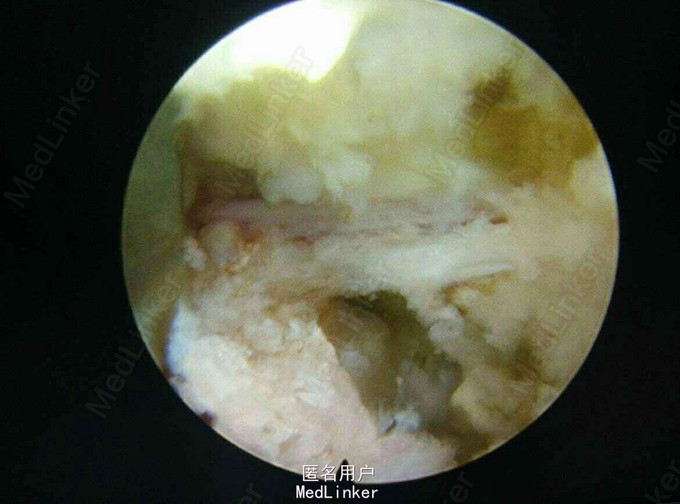

诊断:L45及L5/S1 双节段椎间盘突出(左侧),辅助检查:MRI提示: L45及L5/S1 双节段椎间盘突出,压迫左侧神经根。

术后症状立即缓解,术后两小时佩戴支具下地活动。